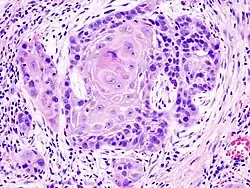

Plattenepithelkarzinome wachsen warzenartig (verrukös) oder ulzerierend und ahmen das verhornende oder nicht-verhornende Plattenepithel in unterschiedlichem Umfang nach. Typisch für sie ist ein Zytoskelett aus Zytokeratin (CK). Hochdifferenzierte Karzinome dieser Entität verhornen und bilden, da die Hornschuppen im Tumorinneren liegen und nicht abgeschilfert werden können, zwiebelschalenartig geschichtete Hornkugeln (Hornperlen), die mikroskopisch meist eindeutig diagnostizierbar sind. Gering differenzierte Karzinome verlieren die Fähigkeit zur Hornbildung. Sie bilden sehr polymorphe (vielformige), solide Tumoren. Sehr stark entdifferenzierte (anaplastische) Plattenepithelkarzinome können in der spindelzelligen (fusiformen) Variante wie Sarkome aussehen.

Als invasiv und damit metastasierungsfähig gelten Plattenepithelkarzinome, wenn sie die Basalmembran durchbrochen haben. Meist lässt sich dann auch eine desmoplastische Stromareaktion (reaktives Bindegewebe) nachweisen. Weitere Zeichen der Invasion sind Einbrüche in Blut- und Lymphgefäße, Perineuralscheideninvasion, destruierendes Wachstum und Metastasen.